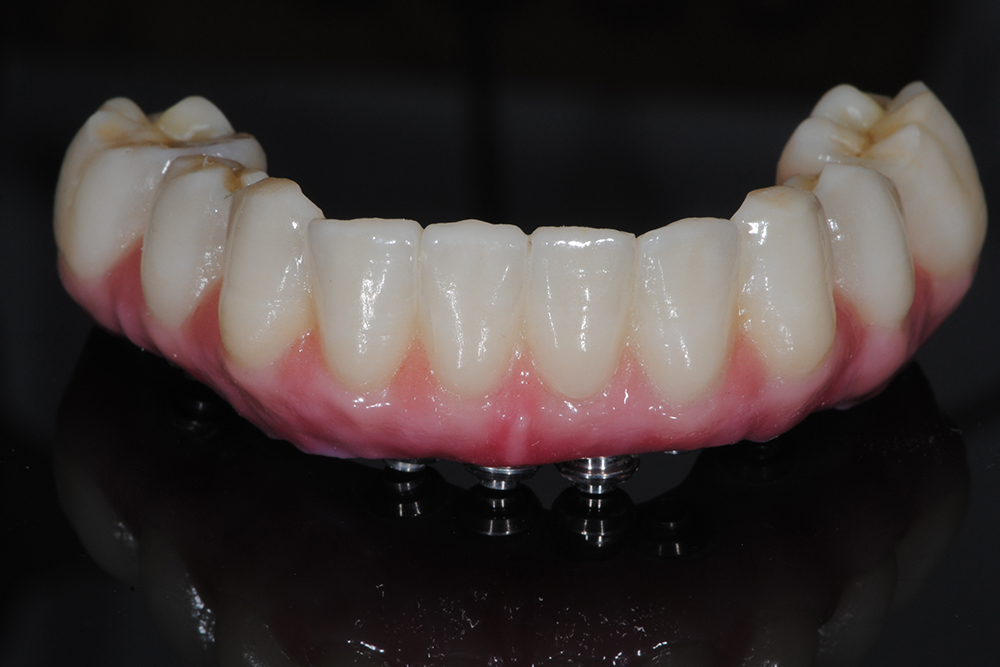

Ripristino dell'arcata inferiore con carico immediato Category: Lavori ImpiantiMaggio 9, 2018Condividi questo ProgettoShare with FacebookShare with TwitterShare with Google+Share with PinterestShare with LinkedInProject navigationPreviousPrevious project:Ripristino dell’arcata superiore su impiantiNextNext project:Ripristino di breccia anteriore inferiore